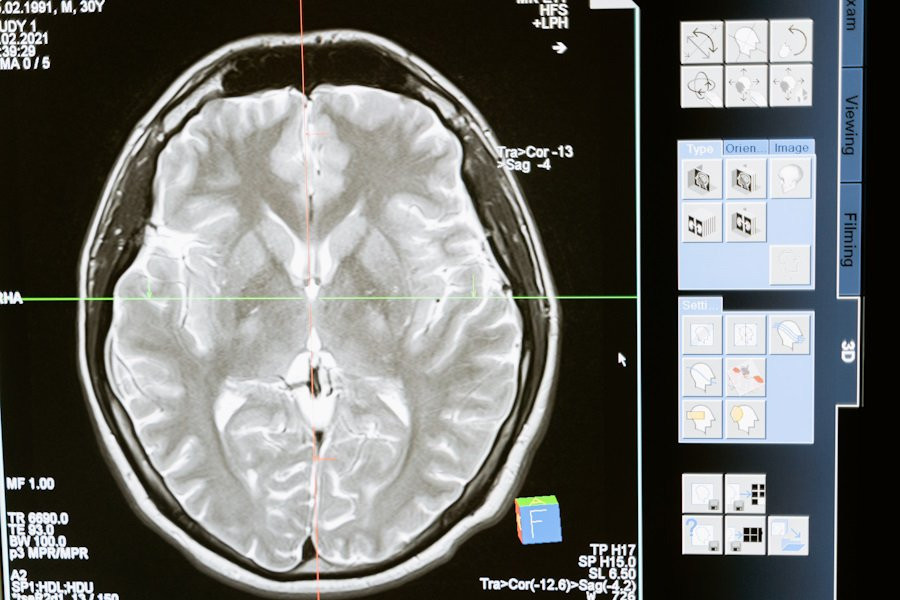

Воспользовавшись функциональной МРТ (фМРТ), специалисты определили конкретную область мозга, отвечающую за руминацию, — это дорсально-медиальная префронтальная кора (ДМПК).

Исследование показало, что ДМПК взаимодействует с другими частями мозга, особенно с левой нижней лобной извилиной и правым височно-теменным соединением. Данная связь играют немаловажную роль в понимании процесса руминации, поскольку эти области мозга связаны с речью и оценкой социальных ситуаций.